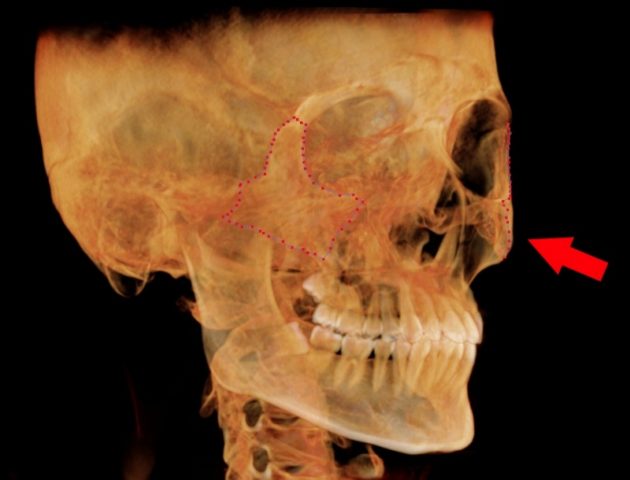

歯性上顎洞炎に なりやすい人 なりにくい人

歯性上顎洞炎になりやすい人

歯根と、上顎洞が近い人です。

上は、上顎洞内に、

大臼歯の歯根が

飛び出しています。

もし、この根が化膿すると、

上顎洞に炎症が波及しやすいでしょう。

この様な方は、

歯性上顎洞炎になりやすいと思われます。

歯性上顎洞炎になりにくい人

上は、上の大臼歯の歯根と、

上顎洞の距離がある方です。

もし、歯根が化膿しても、

炎症は、上顎洞へは、波及しにくいでしょう。

歯性上顎洞炎には、なりにくいと思われます。